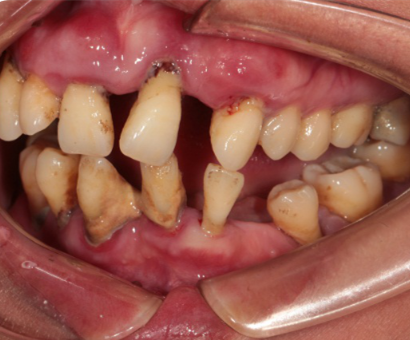

Intraoral Examination(A zone=Right upper jaw、B zone=Left upper jaw、C zone=Left lower jaw、D zone=Right lower jaw)

Poor oral hygiene, accumulation of calculus, three-degree loosening of the entire mouth

Periodontitis causes severe absorption of the upper and lower jaws

A zone A4-A6、B zone B2、C zone C2-C4、D zone D2-D3 lost

A zone A1-A3、A7、B zone B1、B5-B7、C zone C1、C5-C7、D zone D1、D4-D8 all with III°loosen

Photos of preliminary oral diagnosis